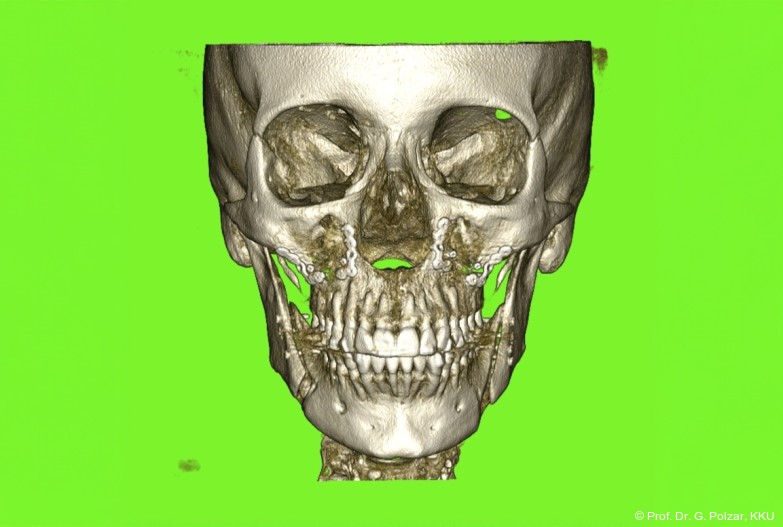

KG-Position: Die 3D-Ansicht im DVT zeigt eine vorverlagerte UK-Position bei neutraler Okklusion (Abb. 4a+b).

Diese deutlich anteriore Gelenkposition im Neutralbiss ließ den Verdacht auf einen Sunday Bite zu. Das heißt, die Patientin schob den Unterkiefer aktiv nach vorne, um damit schönere Schneidezahnkontakte bzw. eine vermeintlich neutrale Okklusion zu erreichen. Nach mühsamen Lockerungsübungen gelang es der Patientin, auch in die zen­trale Kiefergelenkposition zu wechseln. So zeigte sich das ganze Ausmaß der Malokklusion. In neutraler KG-Position hatte die Patientin eine sagittale Frontzahnstufe von ca. 7 mm mit 1 PB Klasse II-Okklusion im Seitenzahn­bereich (Abb.5a+b, 7a–c).